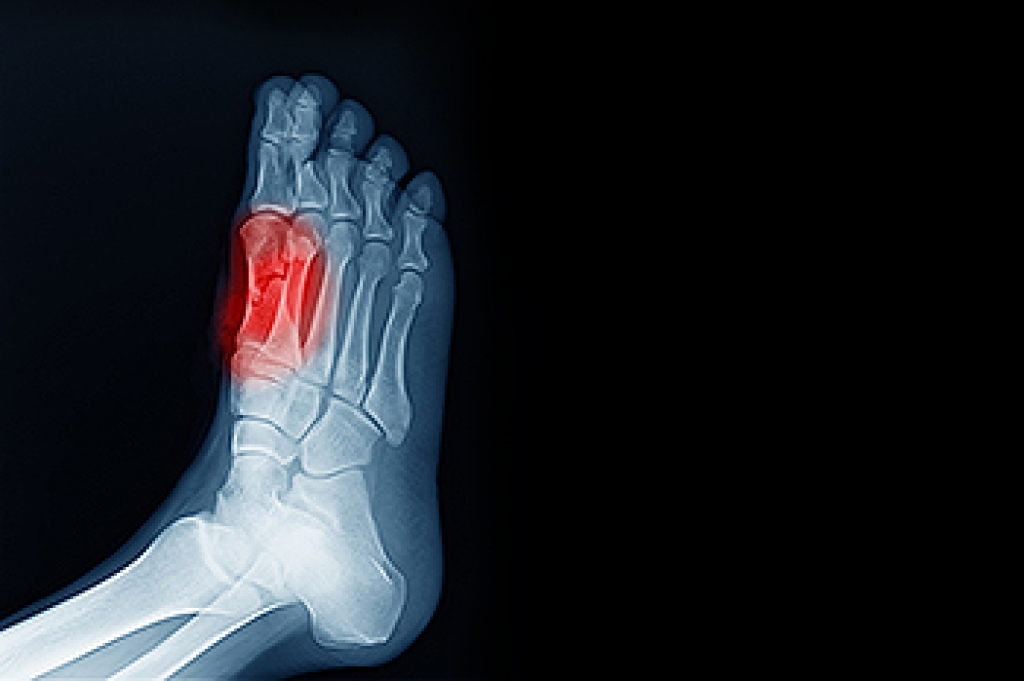

Sesamoiditis is an irritation of the two sesamoid bones that are located beneath the first metatarsal head of the foot. It leads to pain that can be particularly bothersome during activities like walking or running. These tiny bones, each about the size of a kernel of corn, play a significant role in foot movement. They can become painful due to trauma, foot structure changes, or repetitive stress. Sesamoiditis is often seen in dancers, runners, and those who frequently wear high heels. Symptoms can include localized pain beneath the big toe, swelling, and tenderness that worsens with pressure. Diagnosis typically involves a clinical evaluation by a podiatrist, sometimes supported by imaging tests to rule out fractures or other conditions. Treatment focuses on reducing pressure on the sesamoids through footwear modifications, including supportive shoes and custom orthotics. If you have pain under the big toe, it may be related to the sesamoid bones, and it is suggested that you schedule an appointment with a podiatrist for an exam and treatment.

Sesamoiditis is a condition of the foot that affects the ball of the foot. It is more common in younger people than it is in older people. It can also occur with people who have begun a new exercise program, since their bodies are adjusting to the new physical regimen. Pain may also be caused by the inflammation of tendons surrounding the bones. It is important to seek treatment in its early stages because if you ignore the pain, this condition can lead to more serious problems such as severe irritation and bone fractures.